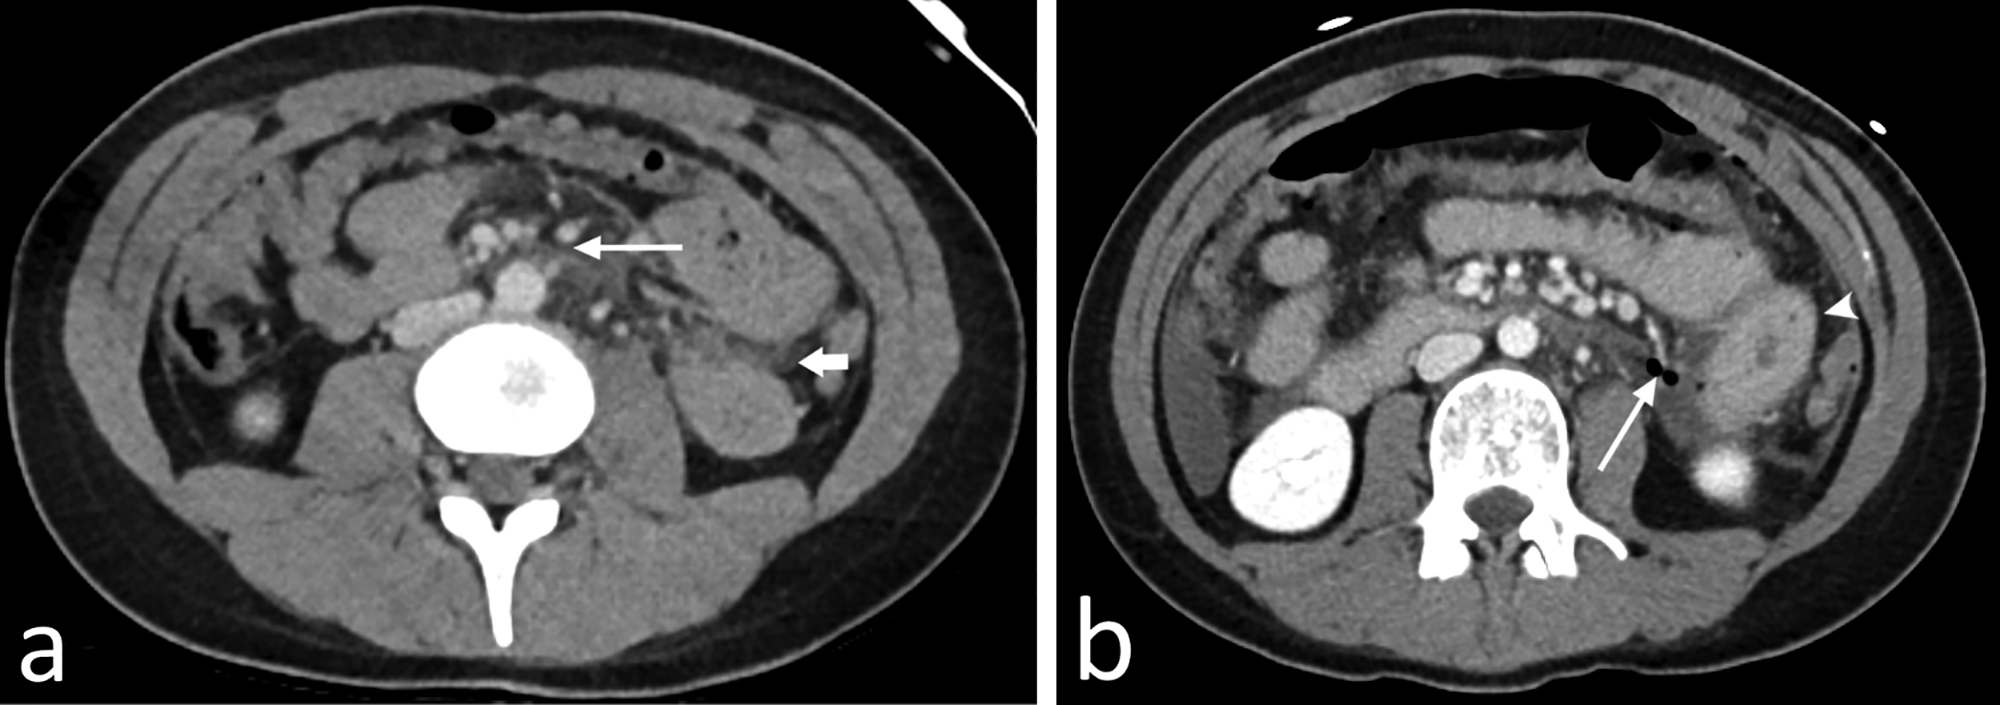

Figure 1

Axial (a) CT in the venous phase of an 18‑year‑old woman who was involved in a car accident at very high speed (200 km/h). She underwent whole‑body CT scan, which only showed subtle mesenteric infiltration central in the abdomen (long arrow) and a minimal amount of free fluid on the left side (short arrow) and in the pouch of Douglas (not shown). Because she was stable and alert and had no abdominal pain, she was admitted for observation. Later, she developed severe abdominal pain, for which a repeat CT scan (b) was performed approximately 10 hours after the initial scan. There is an increased amount of free fluid, a massive pneumoperitoneum with several small air bubbles posteriorly in the abdomen (long arrow), and an adjacent small bowel loop with significant wall thickening (arrowhead). Exploratory laparoscopy confirmed jejunal perforation.